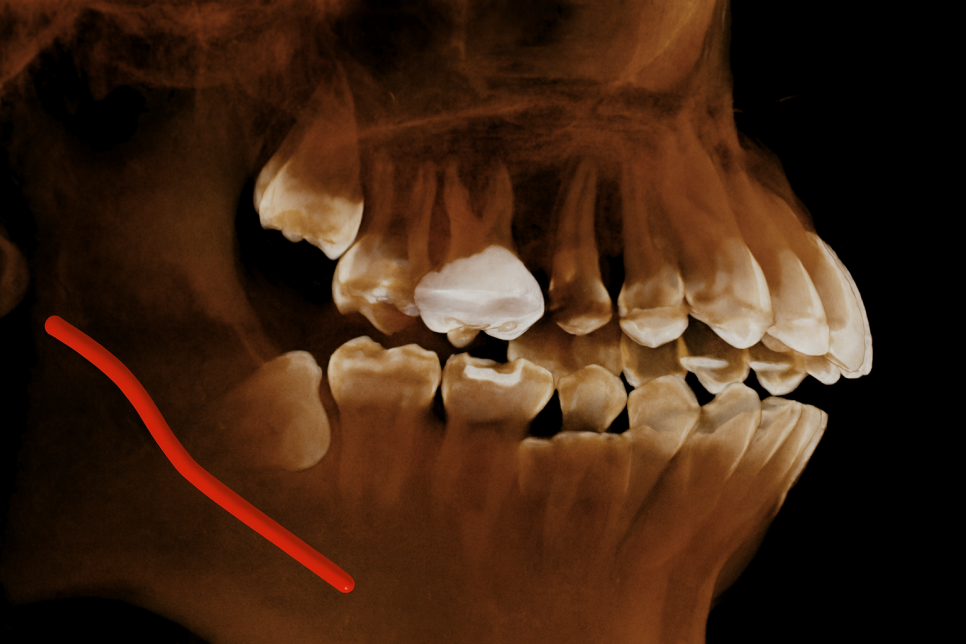

그래서 삼차원적인 자료인 CBCT를 함께 찍어

세밀하게 관찰을 진행하게 되죠.

그 과정을 영등포동 치과 에서 준비한

예시 자료를 보면서 설명해 드리겠습니다.

사진을 보시면 지치 하방으로 주행하고 있으며

거리가 매우 가깝다 판단됩니다.

다만, 맞닿아 있거나 누르고 있는 케이스는 아니라

진료에 필요한 최소한의 거리는 확보되는 상태죠.

이런 경우 통상적으로 분할하여 뽑아주는

방식을 택하게 됩니다.